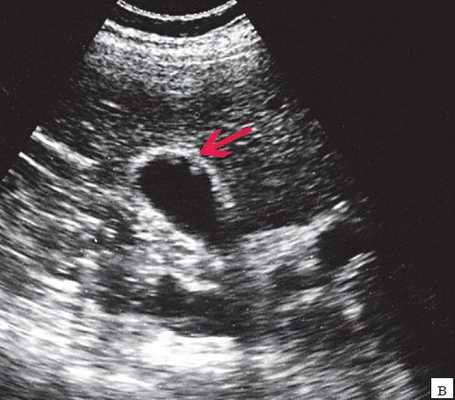

Материалы и методы. Исследование и лечение проводилось на базе детского хирургического стационара МУЗ ГКБ № 20 им. И.С. Берзона г. Красноярска, в котором проходили лечение 25 детей в возрасте от 1 мес. до 14 лет с врожденными кистами желчных протоков. При обследовании детей использовали клинико-лабораторную диагностику и инструментальные методы исследования: УЗИ в 100%, КТ - 50%, интраоперационная холецистография - 40%, ЭРХПГ -20%, лапароскопия - 20%. Эхографически киста общего желчного протока определялось как округлое или овальное анэхогенное образование, локализующееся в области головки поджелудочной железы и не связанное с желчным пузырем. Компьютерная томография полностью подтвердила данные, полученные при сонографическом исследовании. Следует отметить, что использование эндоскопической ретроградной холангиопанкреатографии позволяет выявить наиболее точную картину поражения общего желчного хода при сохранности проходимости в дистальной его части. На основании полученных данных решался вопрос о выборе метода хирургического лечения. Таким образом, дооперационная диагностика кистозной трансформации желчевыводящих путей в настоящее время значительно улучшилась благодаря применению современных методов исследования. Однако, выбор оперативного метода лечения окончательно может быть произведен только во время операции, так как решающее значение в верификации диагноза имеют интраоперационные рентгеноконтрастные методы исследования, которые позволяют выявить кистозные расширения вне- и внутрипеченочных желчных протоков, степень и протяженность их дилятации, проходимость терминального отдела холедоха, рубцовые сужения печеночных протоков, билиопанкреатический рефлюкс. В настоящее время предложен новый метод распознавания и лечения врожденной патологии желчевыводящей системы, включающий в себя комбинированное применение лапароскопии, чрезкожной чрезпеченочной холецистохолангиографии в сочетании с рентгенологическим контролем (под контролем электронно-оптического преобразователя) в режиме реального времени. К положительным сторонам данного метода относится: а) возможность применения у новорожденных детей; б) естественное (антеградное) введение контрастного вещества не допускает развития восходящего холангита; в) минимальная травматичность, г) высокая информативность, д) возможность в некоторых случаях устранять препятствие в области желчного протока.

Ультразвуковое исследование выполнено всем больным детям в 100%, что позволило в 60% поставить диагноз киста холедоха, КТ 7 детям (38%) с целью дифференциальной диагностики и уточнения топического расположения кисты, интраоперационная холецистография в 4 случаях (22 %), ЭРХПГ 3 пациентам (20%), лапароскопия 3 пациентам (20%).